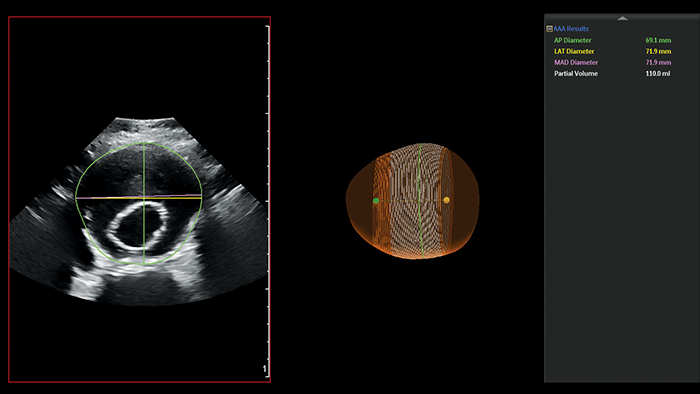

Das AAA-Modell von Philips erfasst, segmentiert und quantifiziert 3D-Ultraschalldaten, die zur Beobachtung von nativen AAAs und AAAs nach EVAR verwendet werden.

Das AAA-Modell von Philips liefert wichtige Messwerte einschließlich des maximalen AP-Durchmessers (Anterior-Posterior) und des partiellen Volumens und zeigt gleichzeitig die Mittellinie des Aneurysmas an.